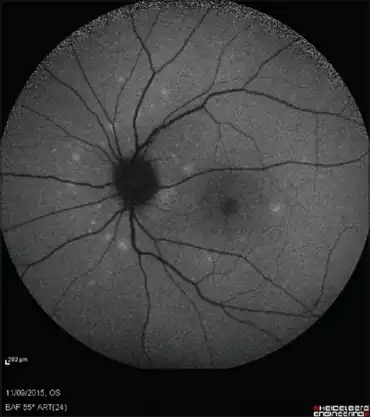

| Multiple white dots concentrated in the peripapillary area | |

- Fundus autofluorescence (FAF) has been shown to be a noninvasive method to demonstrate the subretinal spots in MEWDS.